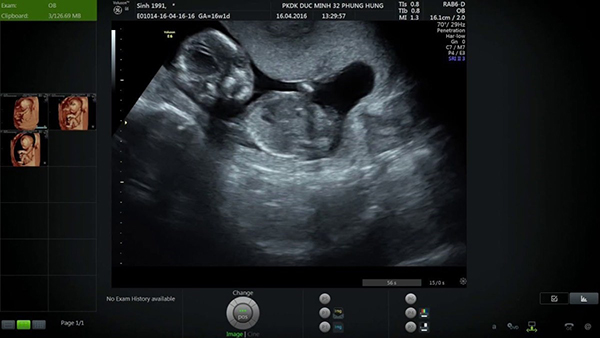

Vào thời điểm siêu âm thai 16 tuần, mẹ sẽ có thể nhận thấy những thay đổi rõ rệt của bé. Điều này có thể sẽ khiến mẹ bất ngờ khi thai nhi phát triển vô cùng nhanh chóng:

Sự thay đổi về bề ngoài của bé bao gồm chiều dài của bé và cân nặng. Lúc này, bé sẽ có cân nặng khoảng 100g và chiều dài khoảng 12cm.

Nhịp tim của bé ở giai đoạn này sẽ đập nhanh hơn so với giai đoạn trước do tim của bé đã được phát triển một cách ổn định. Mẹ có thể thấy rõ điều này trên kết quả siêu âm thai 16 tuần khi nhịp tim của bé là từ 150 đến 180 lần/phút.

Trong hình ảnh siêu âm thai 16 tuần, mẹ có thể sẽ thấy da bé gần như trong suốt. Những mạch máu của bé cũng có thể được nhìn thấy qua làn da mỏng manh này.

Ở thời điểm tuần thứ 16, tuy mắt của bé vẫn còn yếu và nhạy cảm với ánh sáng nhưng mẹ vẫn có thể nhìn thấy sự chuyển động về 2 bên của bé. Sự chuyển động của mắt này rất nhẹ nhàng nhưng việc nhìn thấy ánh mắt của bé khiến nhiều bố mẹ vô cùng hạnh phúc.

Khi siêu âm thai 16 tuần, mẹ sẽ có thể nhìn thấy những cử động đầu tiên của bé. Mẹ cũng có thể cảm nhận những điều này mà không cần qua siêu âm dù những cú đá tay chân của bé vô cùng nhẹ và yếu.